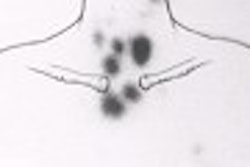

Dr. Paolo Camici, professor of cardiovascular pathophysiology at Imperial College of Science, Technology and Medicine in London, spoke on behalf of PET scanning in heart-disease patients. He noted that FDG-PET allows for the assessment of blood flow and glucose metabolism, especially in patients with the most severe heart failure, and praised FDG-PET’s ability to stratify patients on the basis of risk.

FDG-PET's advantages over SPECT include higher sensitivity, higher specificity, and the ability to measure myocardial blood flow, as well as myocardial metabolism. The latter is important for understanding the pathophysiology of ischemic cardiomyopathy (Nuclear Medicine Communications, April 2002, Vol. 23:4, pp.323-330).